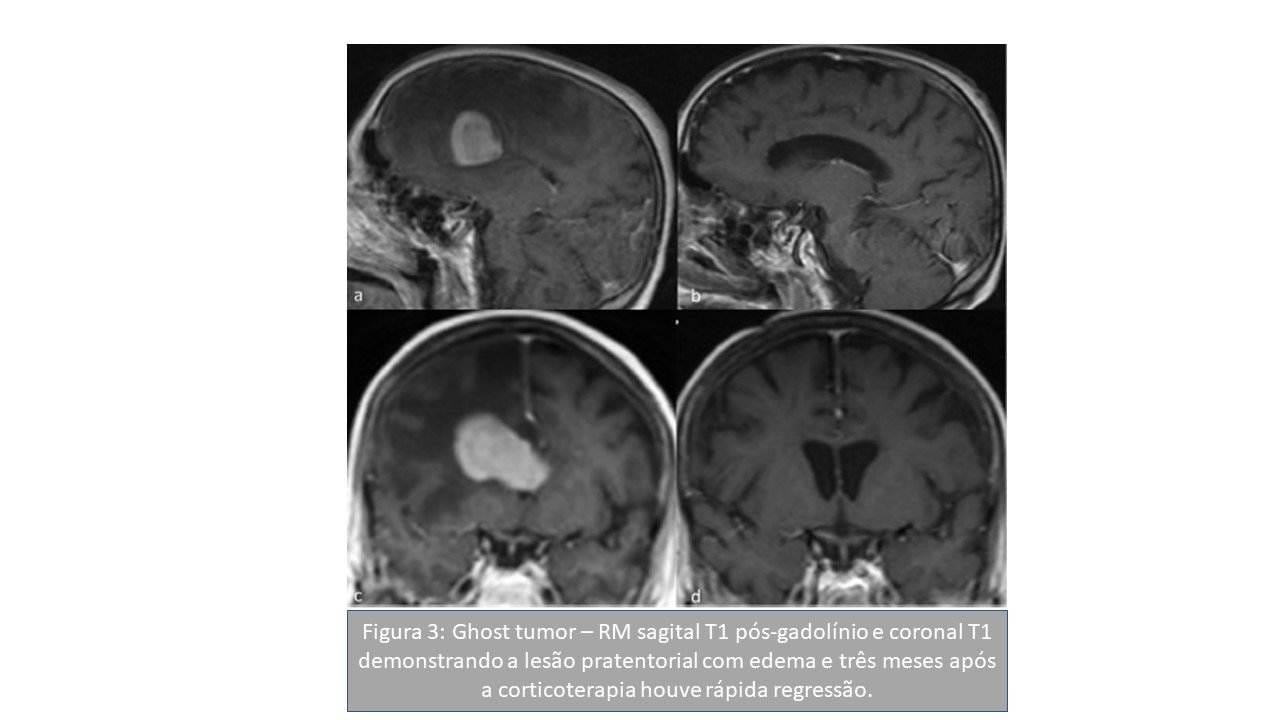

Padrões de imagem na ressonância magnética de linfomas do sistema nervoso central: uma revisão pictórica